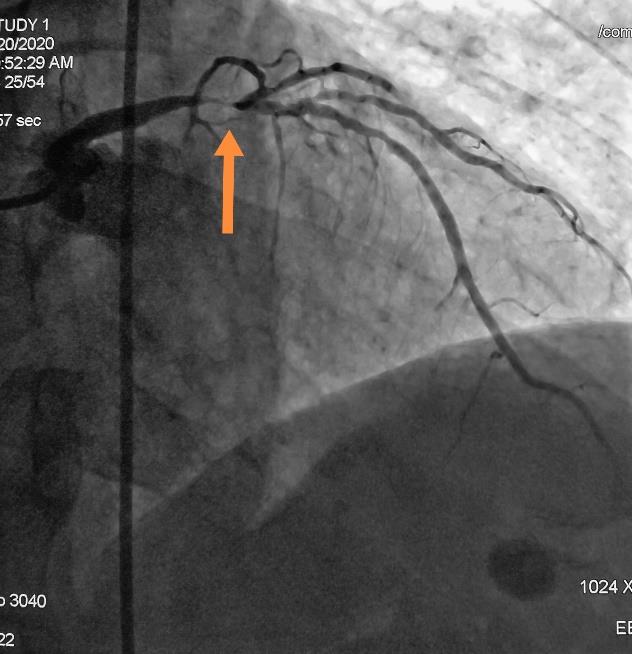

冠脉动脉重度狭窄支架植入术前术后DSA

心内科介入团队为该患者先行冠脉造影提示左侧冠状动脉主干重度狭窄,先行支架植入术。然后,神经介入团队行全脑血管造影术,提示左侧椎动脉重度狭窄,遂行椎动脉支架植入术。术后患者胸闷、胸痛症状消失,头晕症状改善,目前已康复出院。